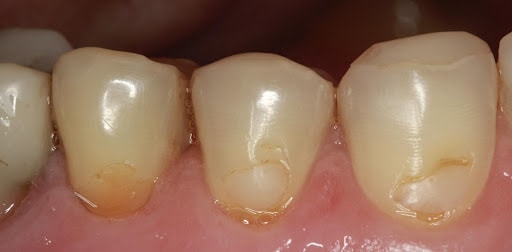

Ryc. 1. Abfrakcja.

Ubytki niepróchnicowego pochodzenia stanowią coraz większy problem kliniczny. Mimo, że pacjenci wciąż borykają się z próchnicą. Erozja, abrazja i abfrakcja stają się często problemem osób zadbanych, z dobrą higieną jamy ustnej i zdrowymi nawykami żywieniowymi. Etiologia ubytków niepróchnicowego pochodzenia jest złożona. Powstają one w wyniku czynników fizycznych i chemicznych w efekcie powodując utratę funkcji, pogorszenie estetyki, nieodwracalną utratę tkanek w różnych lokalizacjach, nadwrażliwość zębów a nawet choroby miazgi 1. Według literatury abfrakcja (Ryc. 1) powstaje na skutek zginania korony zęba pod wpływem obciążeń zgryzowych działających ekscentrycznie do długiej osi zęba. Ale to nie jedyna przyczyna, ponieważ abfrakcji (sprzyja cienka struktura szkliwa i mała gęstość upakowania pasma Huntera-Schregera (HSB) w okolicy szyjki zęba a także liczne czynniki predysponujące, takie jak braki zębowe nieuzupełnione protetycznie, wady zgryzu (głównie stłoczenia, rotacje, inklinacje zębów), konsekwencje periodontopatii – migracje i utrata zębów, parafunkcje, dysfunkcje mięśniowe i stawowe oraz demineralizacja okolicy przyszyjkowej okolicy zębów 2, 3, 4, 5.

Ubytki abfrakcyjne najczęściej dotyczą kłów oraz przedtrzonowców górnych i dolnych. Można je także spotkać na zębach trzonowych. Typową ich lokalizacją jest strona wargowa/policzkową, przy granicy szkliwno cementowej. Jest to widoczne dość dobrze na fotografii Ryc 1. (niestety gdy ubytek już jest - nie jest już widoczna ta granica).

Oba te procesy mogą współistnieć i w tym przypadku bardzo istotny będzie bardzo dokładny wywiad. Najczęściej ubytki abfrakcyjne mają kształt klinu o ostrych krawędziach, czasem nawet poszarpanych. Znajdują się przy granicy szkliwno-cementowej. Początkowo mogą objawiać się tylko jako szczelina w tej okolicy, następnie dochodzi do powiększania się ubytku z zachowaniem charakterystycznego ostrego, klinowanego kształtu. Najczęściej abfrakcję znajdziemy na kłach i przedtrzonowcach (czasem trzonowcach) górnych i dolnych. Abrazja może przybierać różny wygląd zależnie od czynnika sprawczego, zwykle jednak lokalizuje się przyszyjkowo i ma kształt gładkich i regularnych zagłębień - często na kilku sąsiednich zębach. W początkowym okresie mogą to także być płytkie linie czy kreski, zwykle po stronie wargowej. W przypadku abrazji wywołanej przez ścierna pastę do zębów, charakterystyczny jest brak symetrii i jej większe nasilenie na stronie od której pacjent rozpoczyna szczotkowanie (więcej pasty i suche włókna szczoteczki).